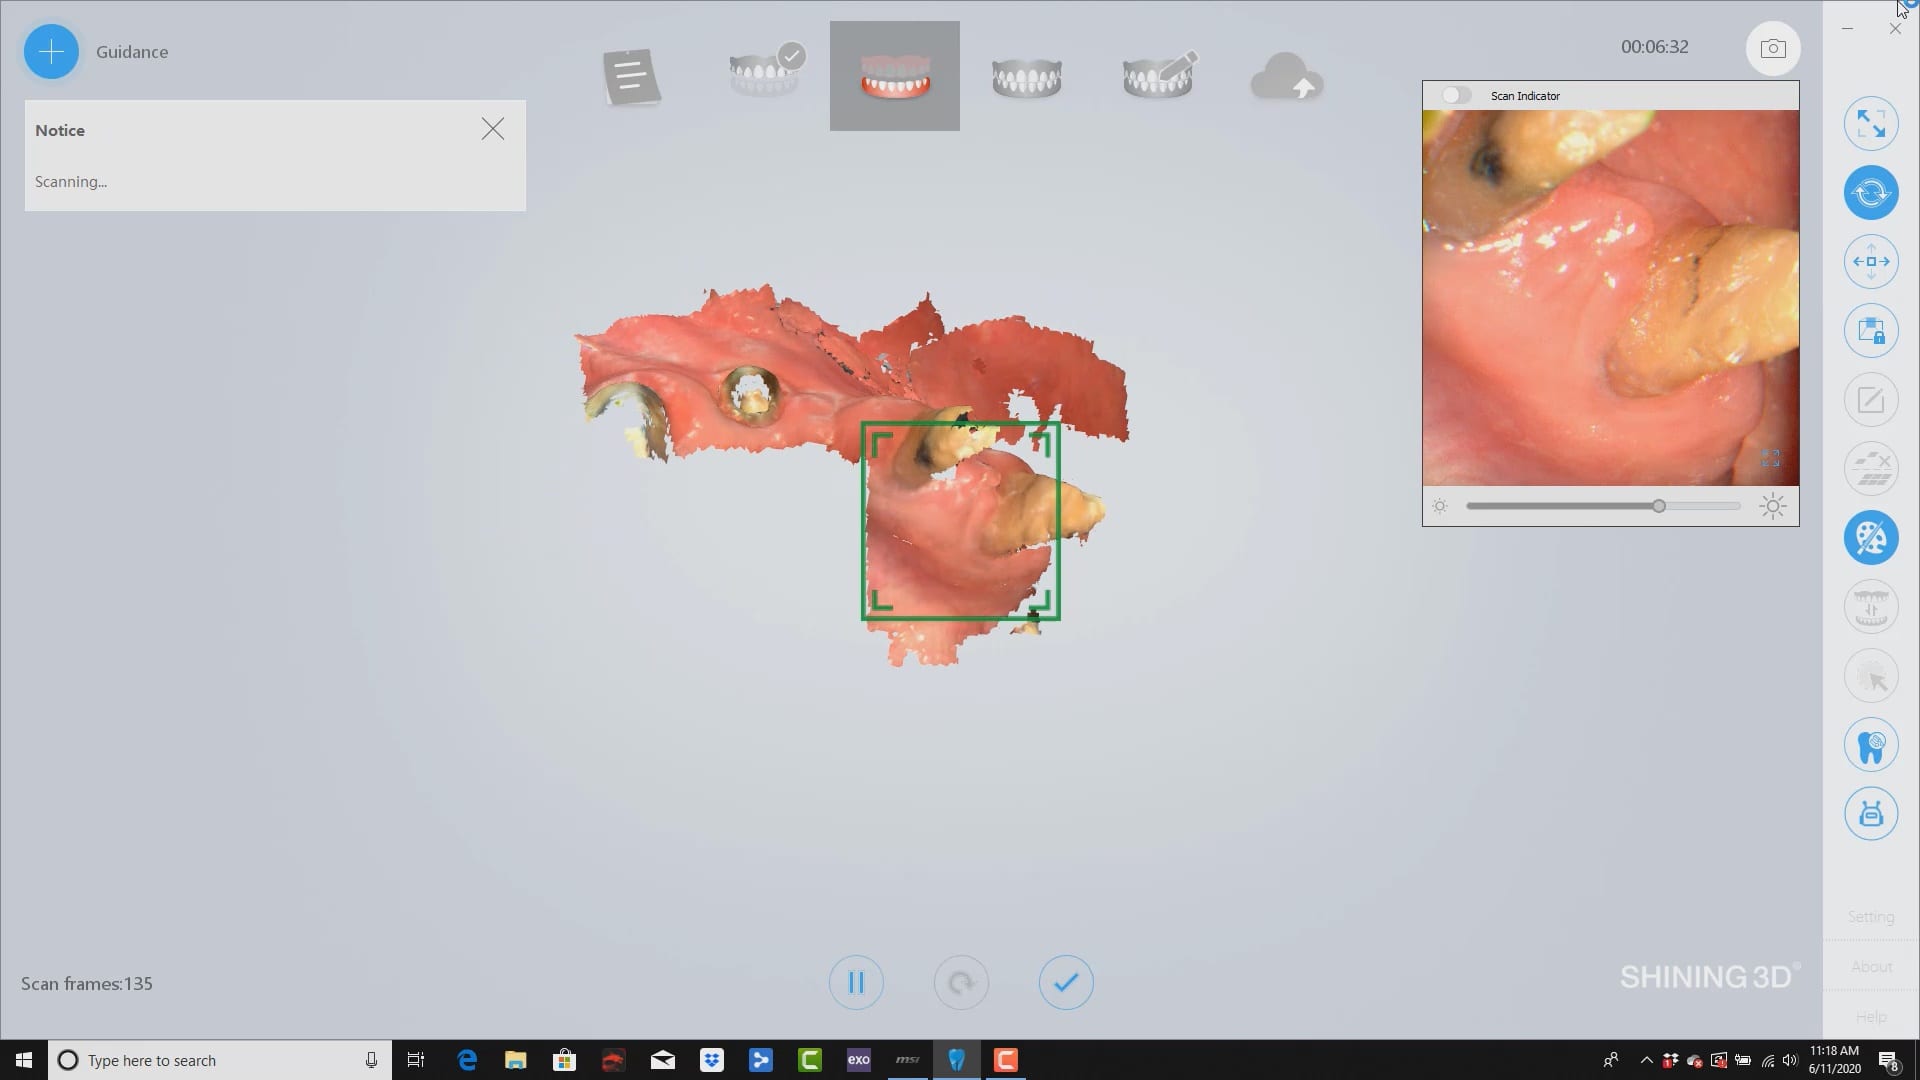

took off lower temps and scanned lower jaw. remaining teeth were used for long term temp abutments while implants healed. digital extractions performed and right vertical dimension for digital prosthesis design

Full arch imaging of mandible in preparation of overdenture